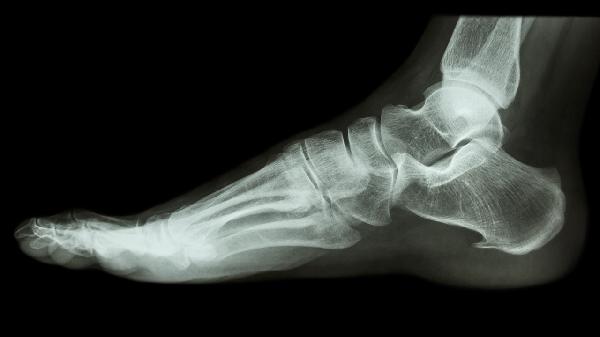

粉碎性或移位性骨折可能导致脚趾短缩、成角或旋转畸形。肉眼可见趾骨轴线异常,与健侧对比明显不对称,开放性骨折可能伴有皮肤破损。

移动患趾时可能听到细微的骨摩擦声骨擦音或触及断端摩擦感骨擦感,此为骨折特异性体征。但非专业人士应避免刻意测试,以免加重损伤。